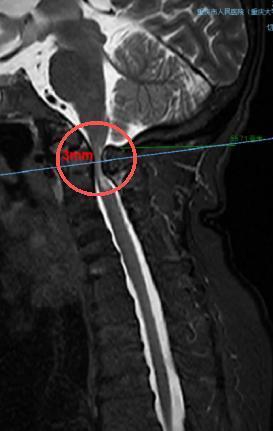

术前,颈椎CT表示寰枢椎脱位(频频为寰椎、枢椎在合并水平线)。重庆市东谈主民病院(重庆大学从属东谈主民病院)供图

术前,颈椎MRI表示,患者脊髓严重受压(圆圈处)。重庆市东谈主民病院(重庆大学从属东谈主民病院)供图 “罗医师,咱们深信你!”尽管深知挑战弘远,但在患者支属的全力委托下,脊柱外科主任医师、该院副院长罗小辑果决接下重任,将患者收治住院。 在了解莫小丽详备病情后,罗小辑速即组织全科相干,并纠合麻醉科、ICU、呼吸科、康复科等进行多学科诊断,为患者量身定制了周详的手术与围术期惩办决策。 多学科合作,买通士命通谈 手术的第一起“死活关”来自麻醉。由于莫小丽身躯矮小、颈部短缩并疯狂,属于十分难堪气谈,气管插管难度极高。所幸,麻醉科主任薛昀及团队凭借丰富的警告和深湛的本领,得胜开发东谈主工气谈,为手术奠定了安全基石。 术中,濒临额外窄小且疯狂的手术视线,脊柱外科团队借助超声骨刀、高速磨钻等顶端开采,以“毫米级”的精度,堤防翼翼地切除患者部分寰椎后弓,达成了受压迫脊髓的绝对减压。